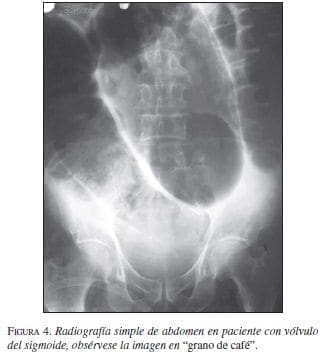

Otra causa de dolor abdominal obstructivo es el vólvulo localizado principalmente en el colon. Su frecuencia varía con base en las diferentes zonas geográficas y aunque su verdadera etiología es motivo de investigación; se sabe que factores como la inactividad física, el uso de medicamentos sedantes, el agrandamiento asintomático con dilatación e hipertrofia de la pared y la elongación del segmento afectado son factores que intervienen en su génesis. En cuanto a su localización, se afectan más el ciego y el sigmoide, en 75% de los casos, dado que el mesenterio en estos segmentos puede estar redundante y alargado; esto propicia que el intestino rote sobre sí mismo. Los síntomas pueden ser de presentación gradual e incluyen dolor tipo cólico, estreñimiento y vómitos. En efecto, el dolor localizado, la sensibilidad dolorosa y una masa mal definida a la palpación sugieren la posibilidad de la enfermedad. En el caso del vólvulo del sigmoides, éste puede resolverse durante la fase aguda con una colonoscopia si no existe compromiso vascular.

El examen inicial para los pacientes con sospecha de obstrucción intestinal es una radiografía simple de abdomen, aunque este estudio imaginológico en la obstrucción intestinal baja es de poca utilidad porque su sensibilidad llega sólo al 49%; sin embargo, la serie de abdomen que incluye las tres proyecciones: de pie, acostado y lateral ofrece mayor información, permitiendo observar la distensión de asas y la presencia de los niveles hidroaéreos, aunque estos últimos en las fases iniciales de la patología pueden estar ausentes (figuras 3 y 4) (59).